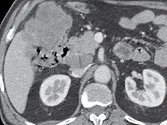

Figure 1. Patient porteur de métastases hépatiques de cancer colique.

Sur l’examen initial (A, B), il existe de multiples lésions secondaires.

Deux cibles sont choisies dans le foie droit, une à hauteur de la bifurcation portale (A) une autre dans le segment VI (B). D’autres lésions mesurables existent, mais seront considérées comme non cible (A). Après six mois de chimiothérapie (C, D), on observe une progression des cibles, des non cibles, et une nouvelle lésion indiscutable dans le segment VI (D)